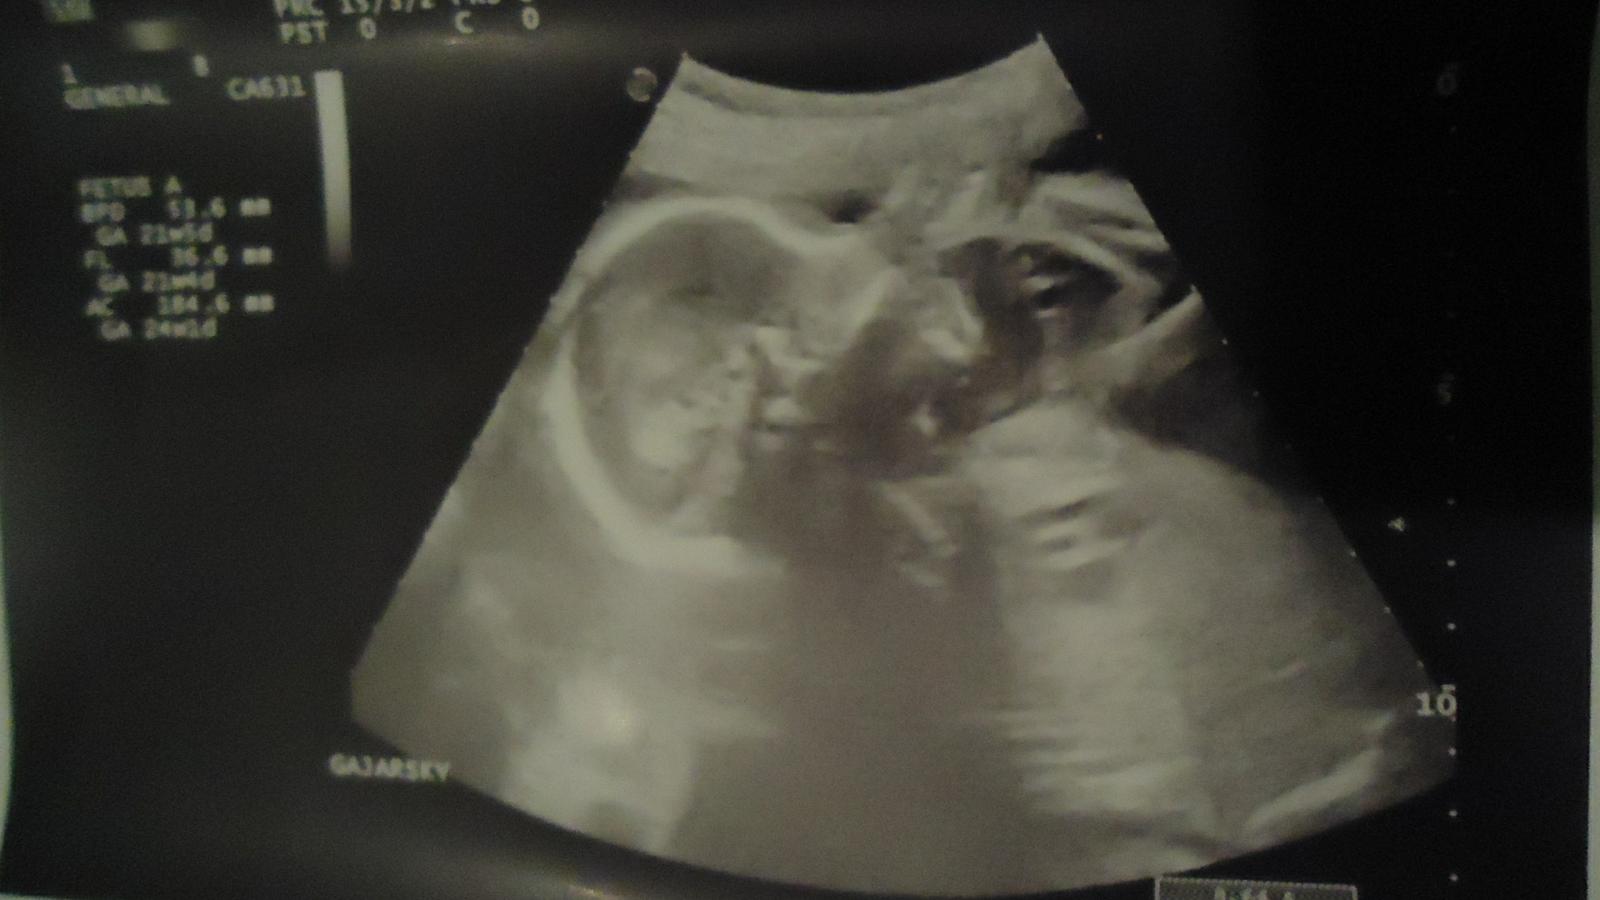

Ahojte babulky tak dnes sono úúúúspešne za sebou a budeme mať chlapčeka takže Filipkovi pribudne braček 😀

Máme 520 gramov sme zdravý a takto krásne si cmúľame palček na ručenke 😀